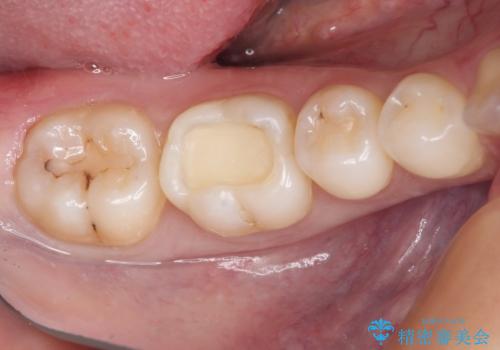

- 他院にてむし歯の治療をし、当院にてセラミックを入れたいとのことで来院された患者様です。

むし歯がないか確認し、セラミックインレーにて修復することとしました。

セラミックインレー装着時には、唾液の侵入を防ぐために、ラバーダム防湿を行いました。

見た目、噛み合わせともに満足していただけました。

ラバーダム防湿を行い、セラミックの接着をすることで、唾液や血液などの接着阻害因子を排除することができます。